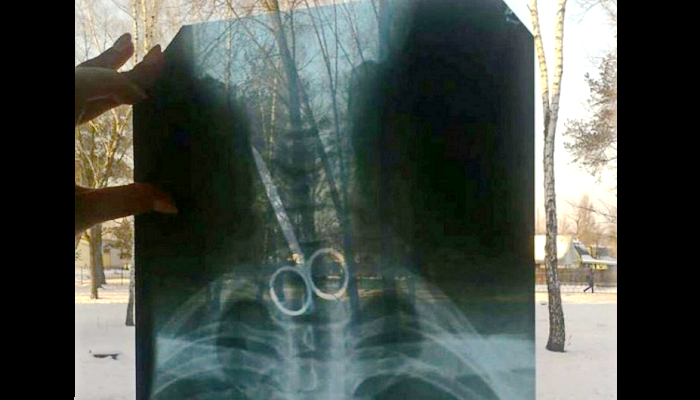

К врачам Черниговской областной больницы обратился местный житель с просьбой осмотреть его. Медики сделали рентген, который показал, что в желудке пациента находятся металлические предметы - ножницы и ложка.

Сейчас имя и возраст мужчины не разглашаются. Однако, стало известно мотив такого поступка. Так, черниговец проглотил предметы на спор.